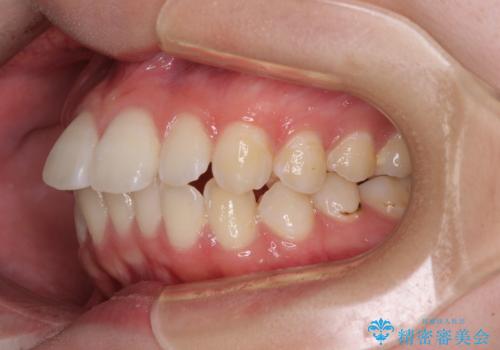

- 飛び出した上の前歯やデコボコを気にして来院された患者様です。

上下前歯の突出感とデコボコを気にして来院された患者様です。

インビザラインによる上下歯列の側方拡大と後方移動、必要に応じてIPR(歯と歯の間を削る)によりスペースの獲得により歯列を整えることとしました。